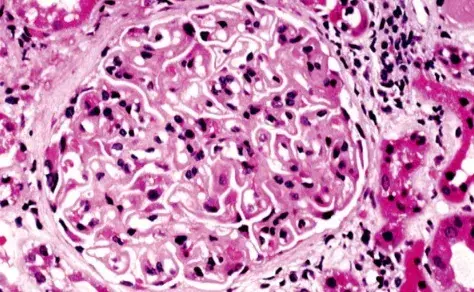

Nefropatía Membranosa: ¿Y si el paciente no responde al tratamiento inicial?

Nefropatía Membranosa: ¿Y si el paciente no responde al tratamiento inicial?

En este video, abordamos estrategias para tratar a pacientes con nefropatía membranosa que no responden al tratamiento inicial. Se enfatiza la importancia de la reevaluación constante y del ajuste del régimen de tratamiento en función de los resultados y del estado del paciente.

Cómo tratar la Nefropatía Membranosa de manera práctica

Cómo tratar la Nefropatía Membranosa de manera práctica